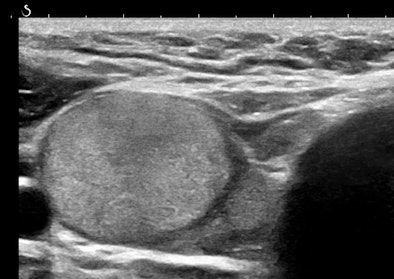

Figures 3A and 3B are the B-mode and simultaneous SWE of a follicular neoplasm of the thyroid. Notice how the elastogram indicates a cell population heterogeneity that is not visible in the original image.

![]() |

| Figures 3A and 3B. |

Homogeneous and heterogeneous are classic ultrasound image features. Perhaps ultimately, refining this descriptor and even quantifying it will be the most important role of SWE in practice.